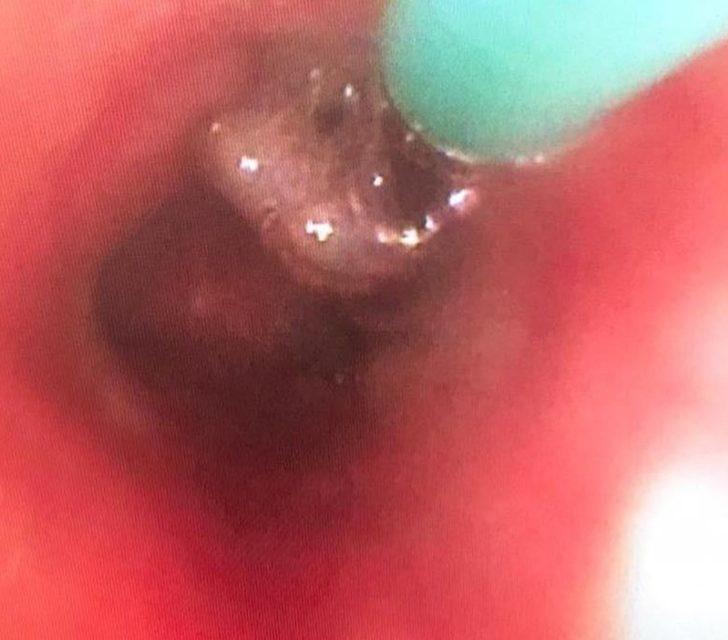

Olayla ilgili bilgi veren Göğüs Hastalıkları AD. Öğretim Üyesi Doç. Dr. Erhan Uğurlu, hastanın polikliniğe 5 gün boyunca süren nefes darlığı ve hırıltı şikayeti ile başvurduğunu kaydetti. Uğurlu, “Nefes güçlüğü çekmesi sonucunda dış merkez başvuruları olan hastaya net bir tanı konulamaması nedeniyle en son gittiği doktor tarafından hastanemize yönlendiriliyor. Hasta polikliniğimize 5 gündür olan nefes darlığı ve hırıltı şikayetiyle başvurdu. Hastanın polikliniğimizde alınan anamnezi ve tipik fizik muayene bulgusu ile karanfil yutmasından şüphelenilerek toraks bilgisayarlı tomografi görüntülemesi yapıldı. Görüntüleme sonucu tanıyı desteklemekteydi. Bu bulgularla hastaya hem kesin tanı hem de tedavi amacıyla Göğüs Hastalıkları Bronkoskopi Ünitesinde bronkoskopi işlemi yapıldı. Sağ akciğer alt lob bronşunda kahverengi yabancı cisim olduğu görüldü ve gerekli malzemeler kullanılarak yabancı cisim (karanfil ) bulunduğu noktadan çıkarıldı. Hastanın tipik anamnezi ve fiziki muayene bulgusu tanı koymamızda kolaylık sağlamış olup şüpheci yaklaşım ve erken tanı ve tedavisi sağlanmıştır” dedi.

Uğurlu, hastanın akciğerine kaçan karanfilin baş ağrısını geçirmesi için çiğnediği sırada gerçekleştiğini ve karanfilin kendisi ile birlikte Araştırma Görevlisi Nilüfer Yiğit tarafından yapılan müdahale ile çıkarıldığını ifade etti. Uğurlu bu tip durumların zatürre gibi komplikasyonları beraberinde getirebileceğini ve hatta ölümle sonuçlanabileceğini de sözlerine ekledi.